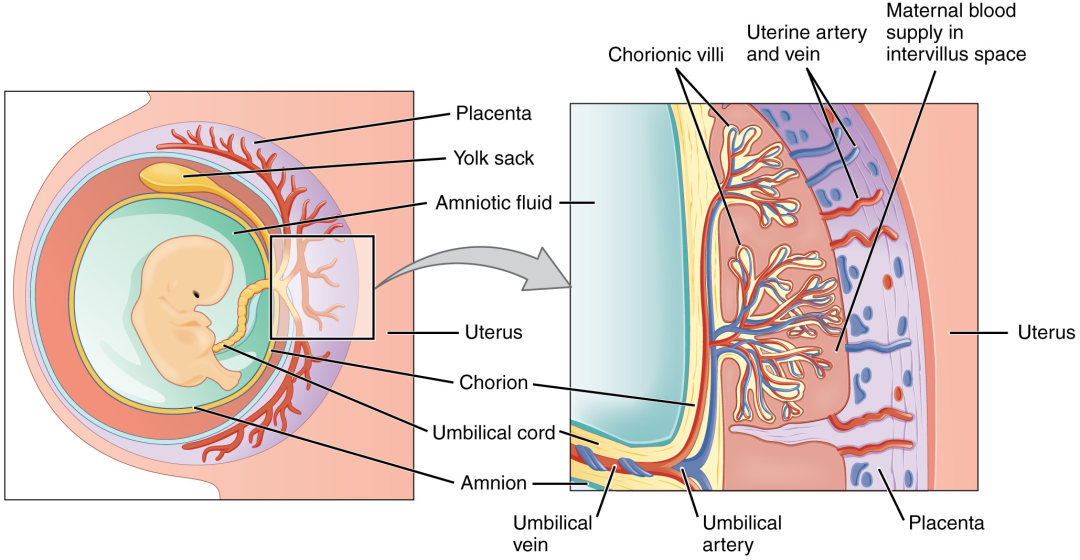

以螺蛳粉为例,当孕妈吃下螺蛳粉时,螺蛳粉中独特的气味分子首先会随着消化道的吸收,进入妈妈的血液。接着「带有螺蛳粉味的血液」在胎盘绒毛的作用下,迅速流向胎盘。

胎盘上有一种特殊的绒毛结构,这种结构有非常强的侵入性,能促进妈妈的血液更快地提供给胎盘。

当「带有螺蛳粉味的血液」充满胎盘的绒毛间隙时,螺蛳粉味的气味小分子物质很容易穿过羊膜,进入到羊水中。

胎盘的结构,气味小分子物质很容易穿过,并进入到羊水中。

图片来源:OpenStax 学院